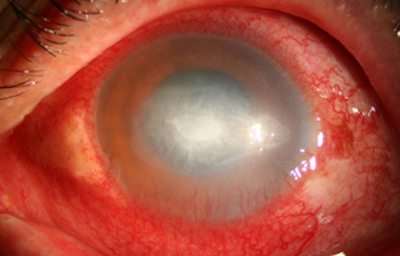

Superficie corneal irregular y grisácea, (Fig. 1, 2) con opácidades granulares en parche y formación de líneas epiteliales elevadas de aspecto granular (Fig. 3), que pueden arborizar dando imágenes de pseudodendritas. Opacidades superficiales satélites. (Figura 4) Inyección ciliar. Ulceración epitelial variante. (Figura 5).

Estas lesiones progresan con la aparición de infiltrados estromales anteriores difusos o focales, (Figura 6) edema circunscrito, y en ocasiones infiltrados en los nervios corneales (Figura 7), (perineuritis, usualmente entre las 1 a 4 semanas de evolución).

En su evolución se observará aumento del edema, agrandamiento y coalescencia de los infiltrados formando un anillo, (Figura 9, 10 y 11) que progresa hacia la formación de un absceso (Figura 12, 13 y 14), queratolisis superficial, adelgazamiento y perforación corneal (Figura 15 y 16).

Limbitis y escleritis anterior difusas.

En los estados avanzados con abscesificación y queratolisis, se enmascara el cuadro corneal, ocultando las características clínicas típicas de la queratitis por Acanthamoeba. (Fig 18)